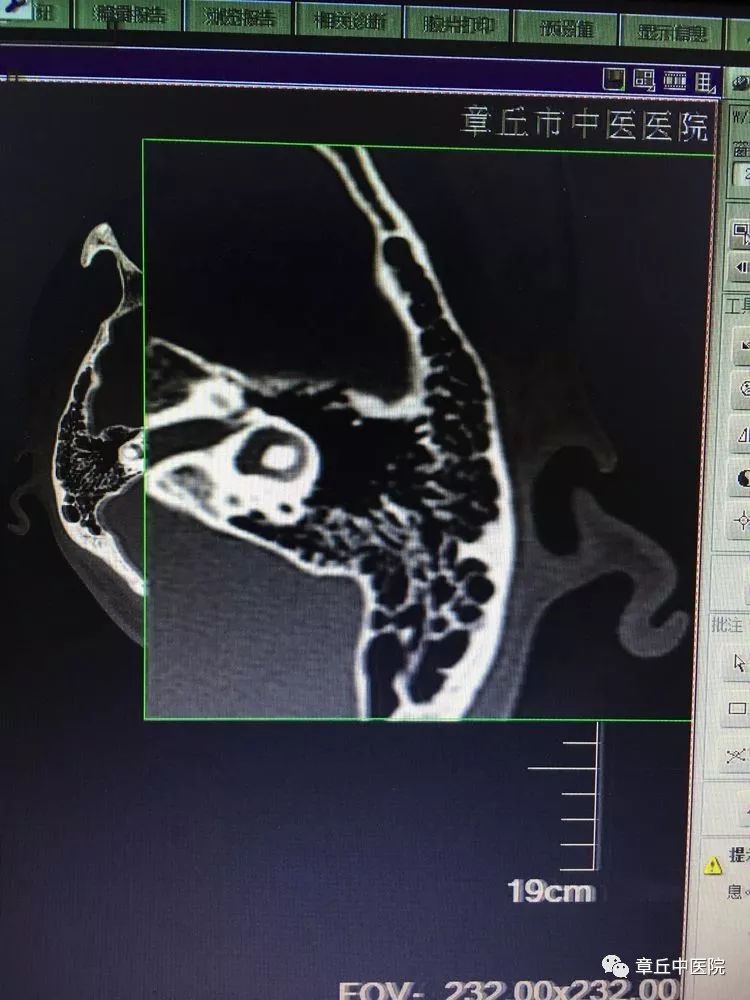

图1耳石症可分为半规管耳石症(或称管结石)和壶腹耳石症(或称嵴顶结石